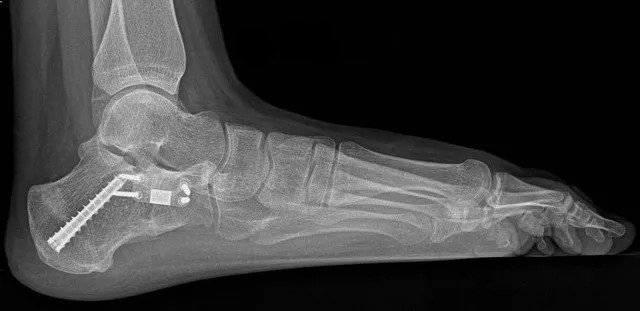

الجراحة ليست إجراءً موحدًا، بل خطة مصممة خصيصًا لكل مريض بعد تقييم دقيق بالأشعة السينية والرنين المغناطيسي.

عملية الفلات فوت

جراحات الفلات فوت ليست إجراءً واحدًا ثابتًا، بل مجموعة من التقنيات الجراحية التي يتم اختيارها وفقًا لطبيعة التشوه ودرجته وحالة الأوتار والمفاصل. الهدف الأساسي من عمليات الفلات فوت هو إعادة بناء قوس القدم واستعادة التوازن الطبيعي للحركة.

أنواع عمليات الفلات فوت:

• قطع العظام (Osteotomy): إعادة محاذاة أو إعادة تشكيل عظام القدم لاستعادة القوس الطبيعي وتحسين توزيع الوزن أثناء المشي.

• إصلاح أو نقل الأوتار (Tendon Transfer/Repair): استخدام وتر سليم من نفس القدم لدعم أو استبدال وتر Tibialis Posterior المتضرر، لتحسين وظيفة القدم وحركتها.

• دمج العظام (Arthrodesis/Fusion): تثبيت مفاصل معينة في القدم لتصحيح التشوه وتحقيق استقرار دائم، عادةً للحالات الشديدة أو المزمنة التي لا تستجيب لتقنيات تعديل العظام فقط.

• إجراءات الأنسجة الرخوة (Soft Tissue Procedures): شد أو إعادة بناء الأربطة لتعزيز البنية الداخلية للقدم وتحسين الاستقرار.

• تقنيات مركبة (Combined Techniques): كثير من الحالات تتطلب دمج أكثر من إجراء معًا للحصول على أفضل نتيجة وظيفية وجمالية للقدم.